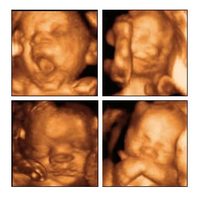

Gracias a la ciencia, los métodos de diagnóstico prenatal son cada vez más complejos. La ecografía tridimensional en tiempo real en movimiento o 4D es una nueva tecnología al servicio del seguimiento clínico del embarazo que aporta más...